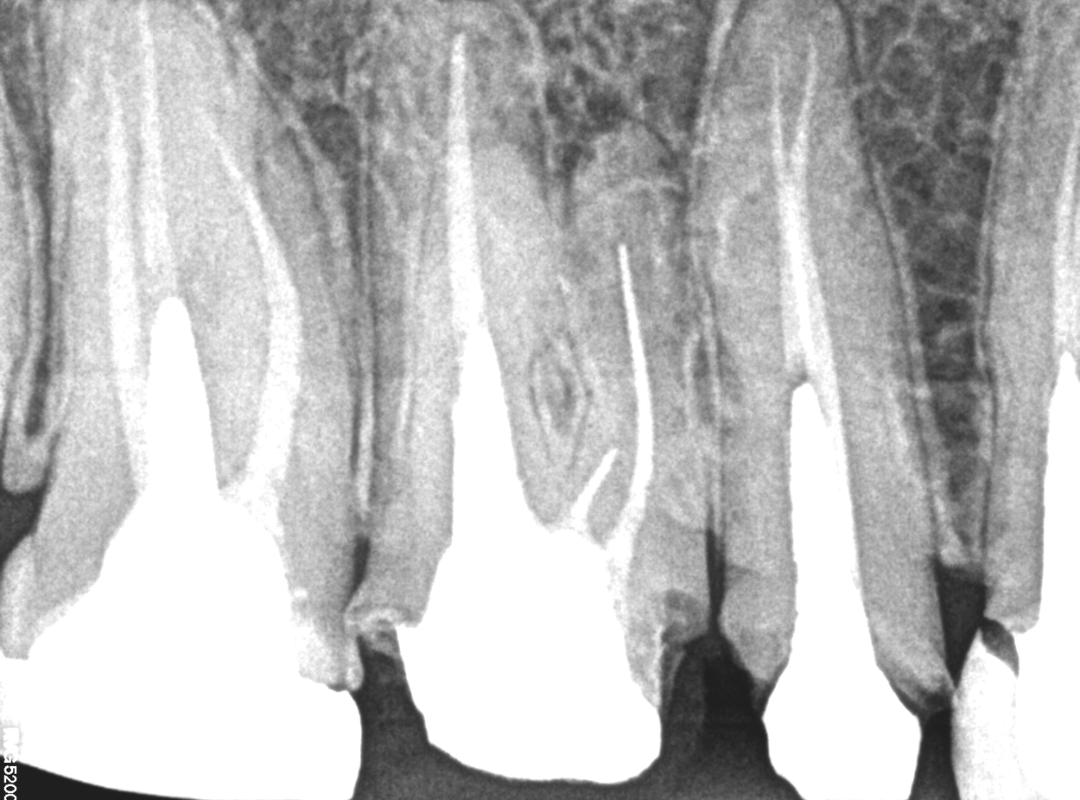

Remoção de Cones de Prata

REMOÇÃO DE CONES DE PRATA NOS CANAIS MV e ML